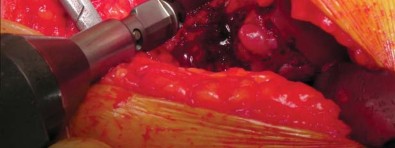

تحضير الفخذ والحق

يتم تحديد مستوى قطع عنق الفخذ مسبقًا بالتخطيط (باستخدام الأشعة السينية) ومواءمته أثناء الجراحة مع المدور الكبير. بعد قطع عنق الفخذ، يتم تحضير الحُق بالطريقة القياسية قبل تحضير الفخذ. يفضل الأستاذ الدكتور محمد هطيف عادةً وضع الكأس وفقًا للمعالم التشريحية لإعادة إنشاء التوجيه الطبيعي للحُق لدى المريض ويتحقق من الإصدار والميل الصحيحين عن طريق الجس والرؤية المباش